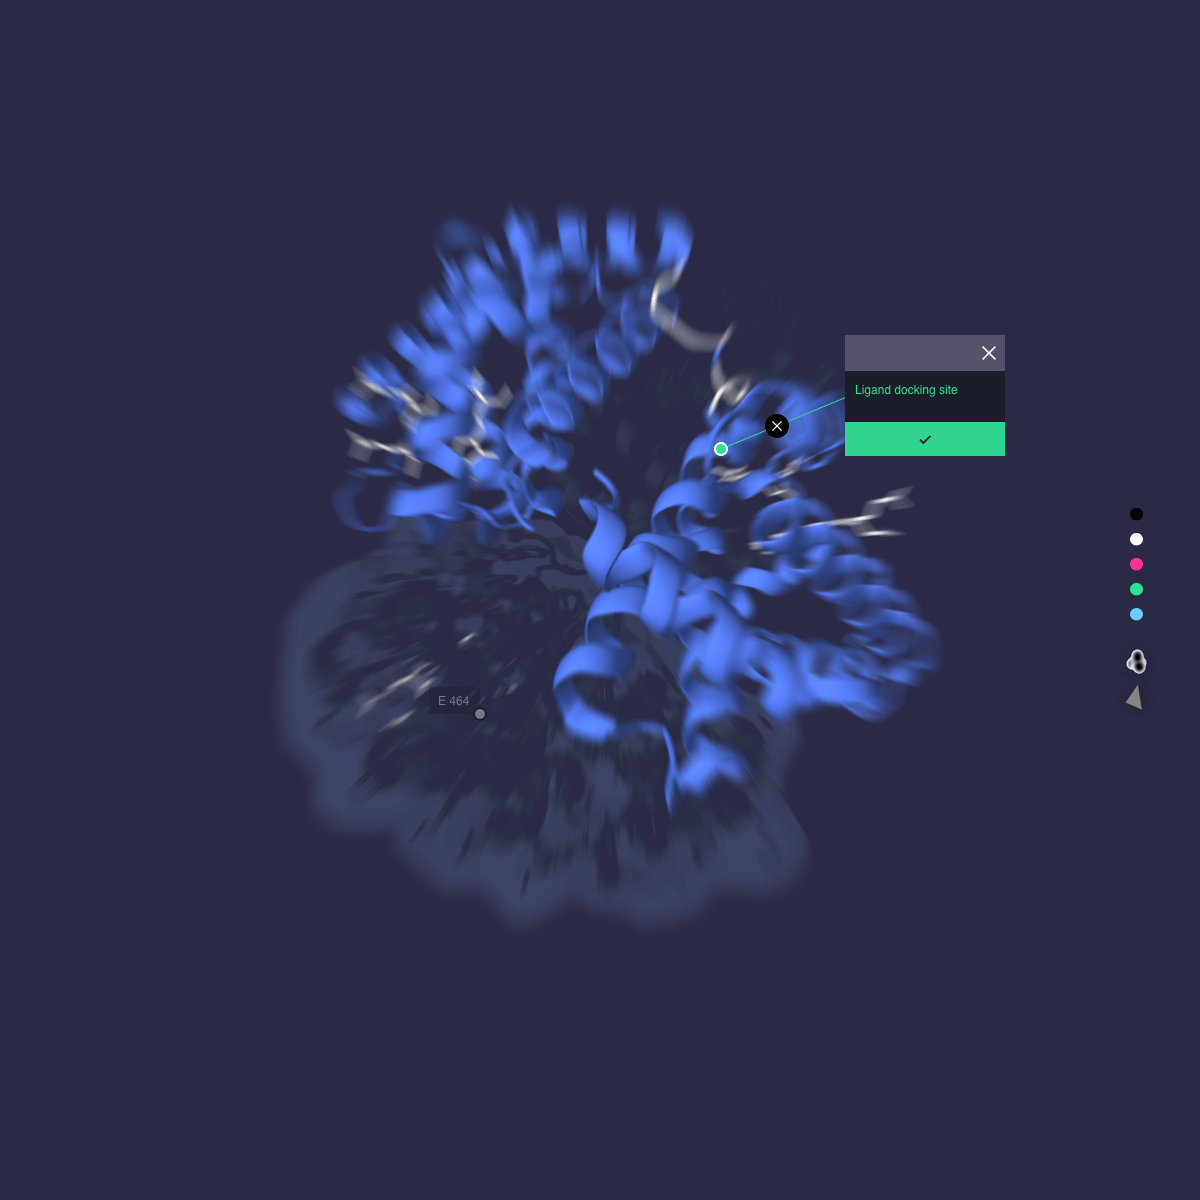

Application

Application

Outcome

Autodesk Molecule Viewer created a new standard in molecular visualization. The application was featured in Nature Magazine and the London Museum of Design.